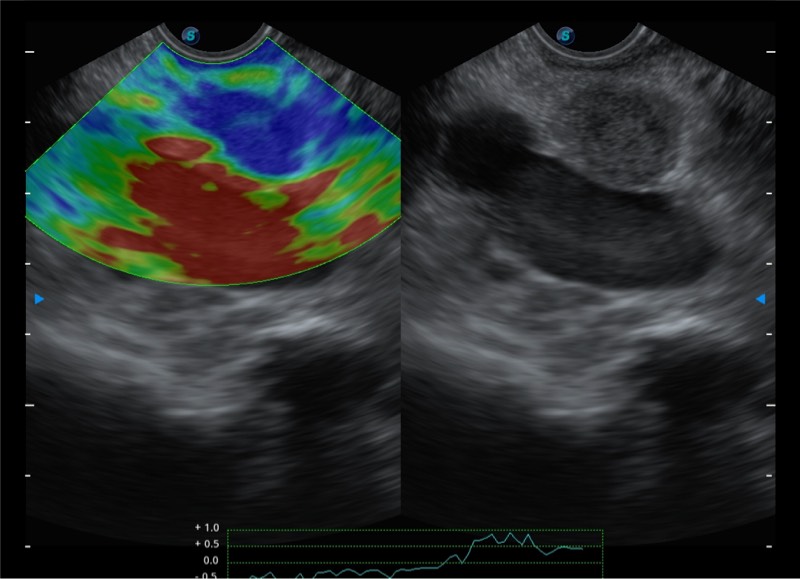

搭载百万级CMOS成像技术

及自主研发凸阵换能器,

可呈现优质的内镜和超声画面

基于二十年的超声技术积累,银河集团官网提供了最新一代的独立超声主机,在提供高质量图像的同时满足多学科使用。具备常见多普勒技术并提供弹性成像、声学造影等高端影像技术。新一代传感器具有更强的抗干扰能力并减少图像伪影。